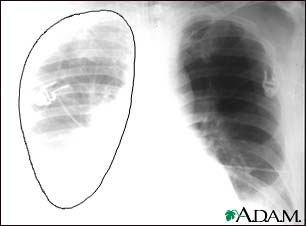

Aortic rupture, chest X-ray

Aortic rupture (a tear in the aorta, which is the major artery coming from the heart) can be seen on a chest x-ray. In this case, it was caused by a traumatic perforation of the thoracic aorta. This is how the x-ray appears when the chest is full of blood (right-sided hemothorax) seen here as cloudiness on the left side of the picture.